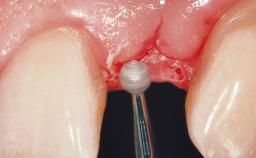

A 29-year-old female patient presented for treatment to replace the upper left central incisor tooth with an implant- supported restoration. The tooth had been intermittently symptomatic for the previous 12 months. The tooth had originally suffered trauma about 15 years previously. Several endodontic treatments had been performed, including an apicectomy procedure to retain the tooth. The patient was healthy and a non-smoker. She had reasonable expectations in regard to esthetic outcomes and the risk of marginal tissue recession following treatment. At medium smile, the gingival margins of the upper teeth were visible, with a display of 3 to 4 mm of the gingival margins. Gingival recession of tooth 21 and a discrepancy in the gingival levels between teeth 11 and 21 was observable during normal speech and smile.

| Placement Protocol | Immediate implant placement |

| Tooth Site | Maxillary incisor or canine |

| Socket Morphology | Single-root socket |